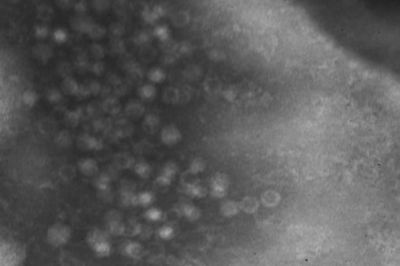

Canine parvovirus (CPV) is currently the most significant canine pathogen in the Czech Republic. In terms of the latest taxonomy, CPV is a strain of the carnivore protoparvovirus 1, the genus of Protoparvovirus, the sub-family of Parvovirinae and the family of Parvoviridae. From the genetic and antigen aspects, CPV is closely related to other strains of carnivore protoparvovirus 1 – feline parvovirus (FPV), mink enteritis virus (MEV) and raccoon parvovirus (RaPV).